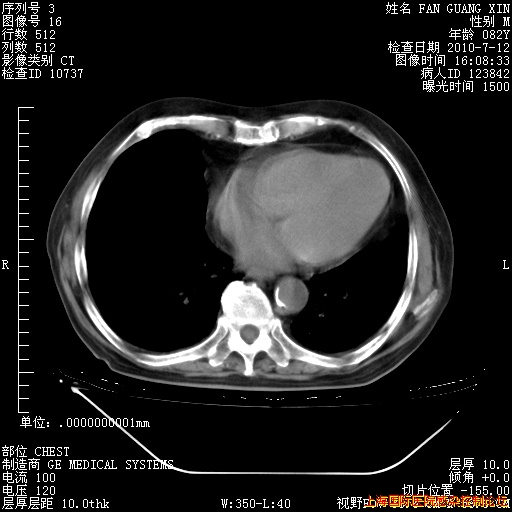

6月12日肺窗

6月12日纵膈窗